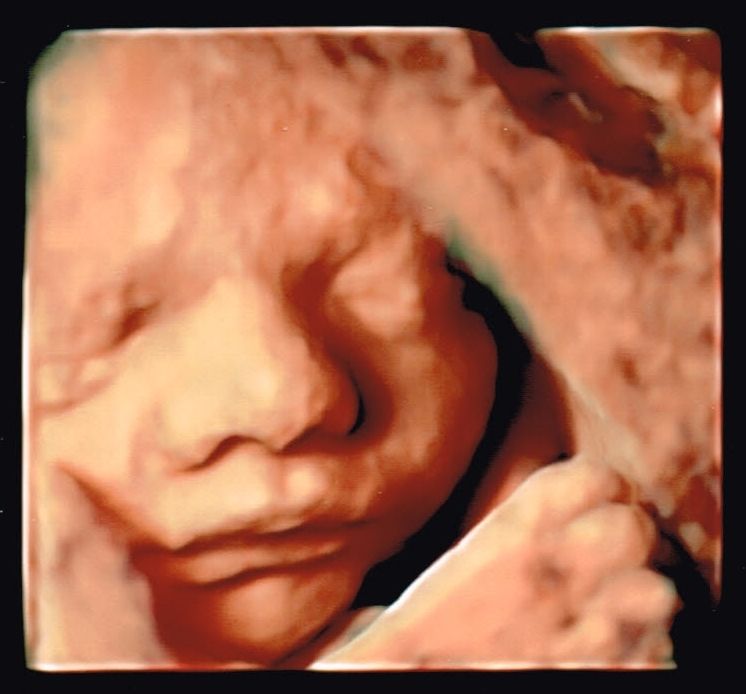

Moją pasją jest diagnostyka ultrasonograficzna w ginekologii i położnictwie, ocena anatomii płodu w badaniach prenatalnych. Nieustająco podnoszę kwalifikacje celem zapewnienia pacjentowi najlepszej opieki. Posiadam certyfikaty Polskiego Towarzystwa Ginekologów i Położników, Polskiego Towarzystwa Ultrasonografii oraz Fetal Medicine Foundation do wykonywania badań ultrasonograficznych.